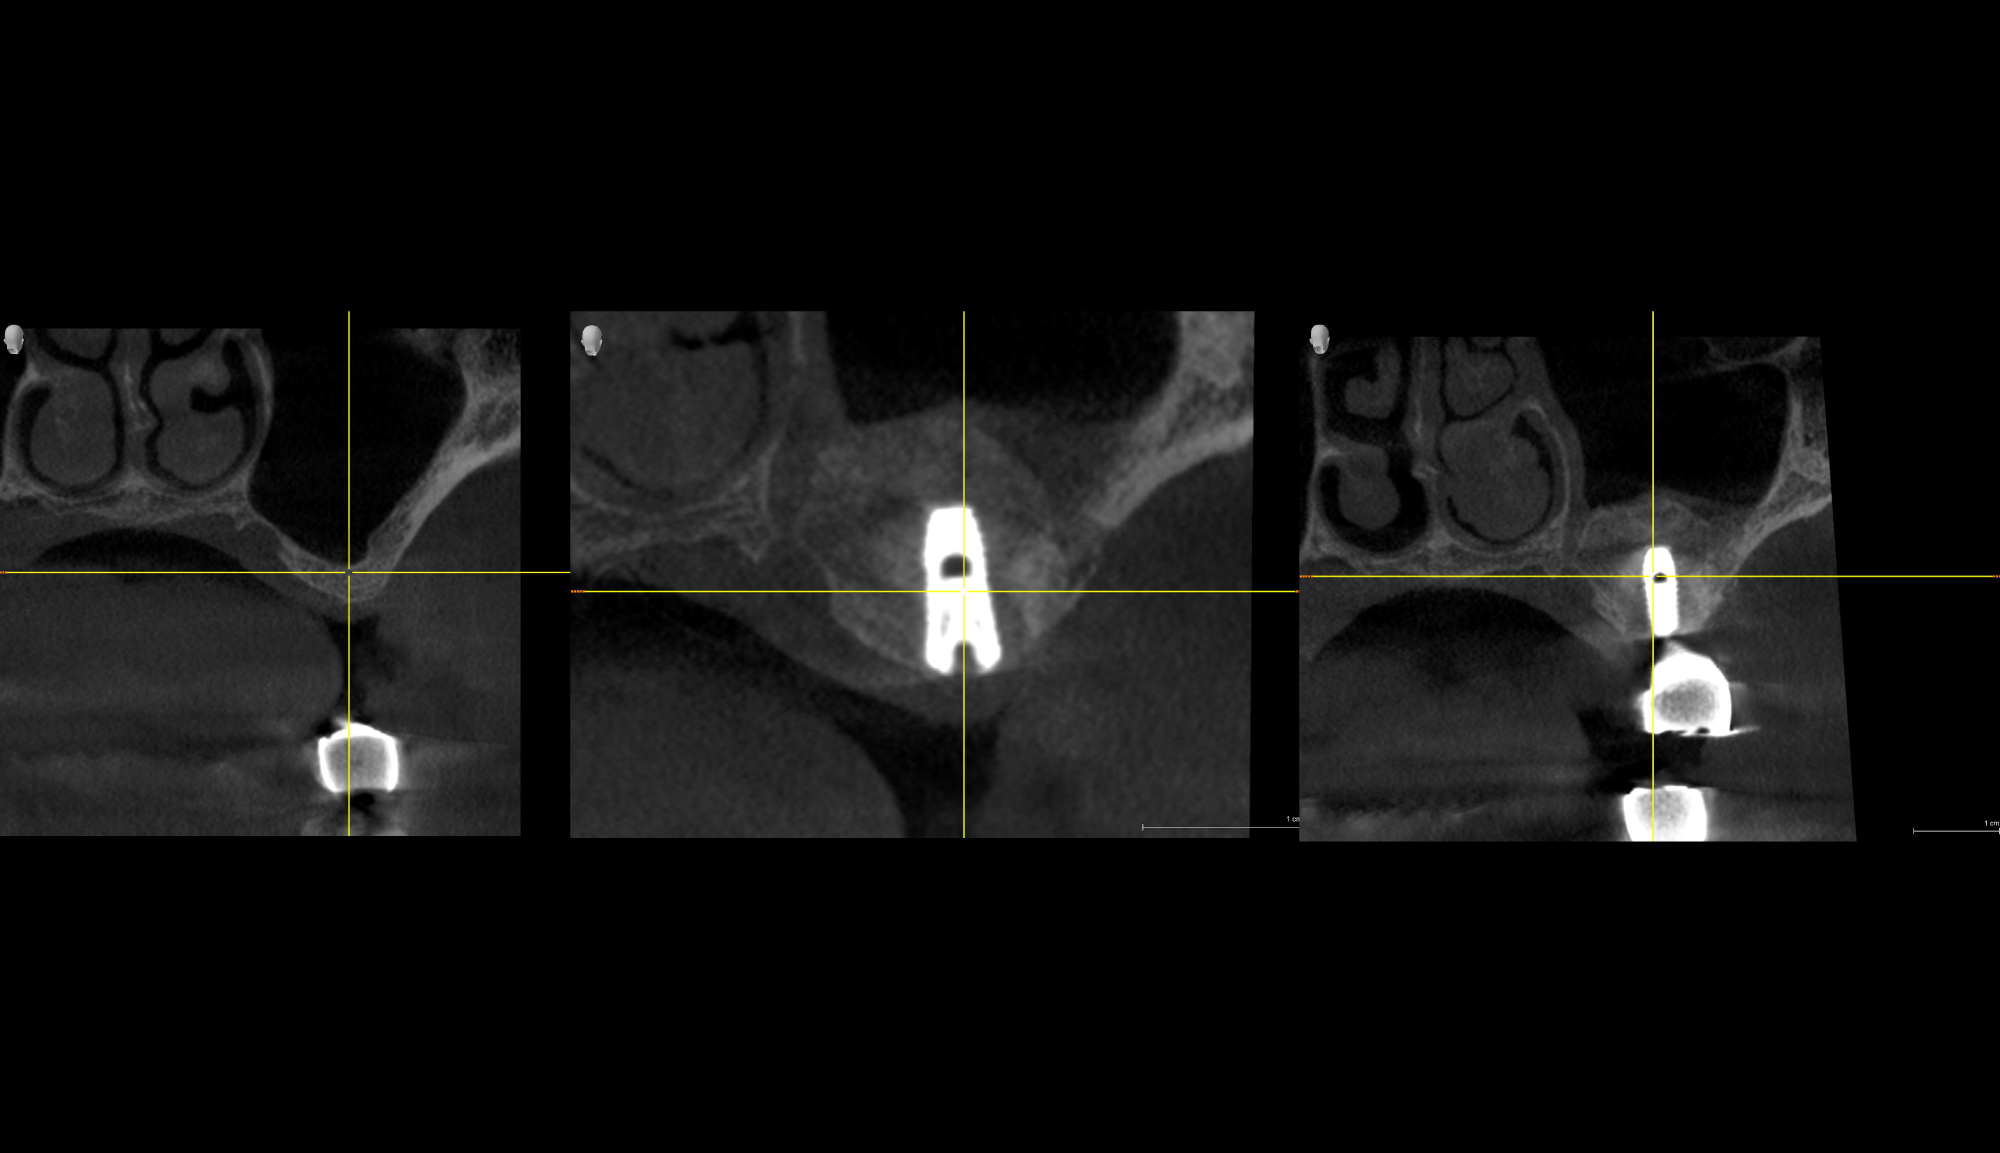

Director’s Clinical Cases

Director’s Clinical Cases